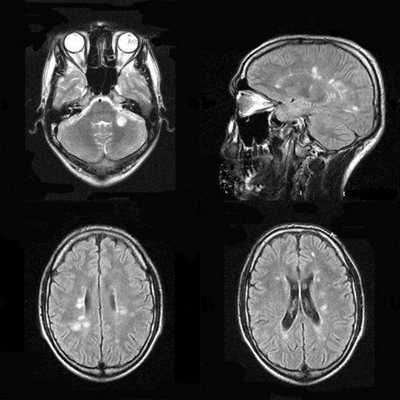

При энцефалите головного мозга на МРТ регистрируют:

Признаки отека головного мозга - сглаженность извилин, уменьшение различий между корой и белым веществом мозга (масс-эффект).

В подостром периоде очаги кровоизлияний в виде усиления сигнала на Т-2 зависимых снимках МРТ и выпадения МР-сигнала в GRE/SWI последовательностях.

Для уточнения данных проводят МРТ с контрастированием. Контрастное вещество накапливается вдоль извилин, по ходу субарахноидального пространства, диффузно или кольцевидно.

Используют разные режимы МРТ диагностики энцефалита, наиболее чувствительным из которых будет импульсная последовательность FLAIR или TIRM: регистрируют сигнал повышенной интенсивности в области коры и сразу под ней.

Для наиболее раннего выявления энцефалита рекомендуют выполнение мультипланарной МРТ в режиме Т2-ВИ, FLAIR или ДВИ, исследование с контрастом в режиме Т1-ВИ. При этом изменения на МРТ обнаруживают раньше, чем на КТ на 1 - 2 суток. Также на МРТ изображениях больше видны последствия кровоизлияний спустя 7 дней от появления симптомов.